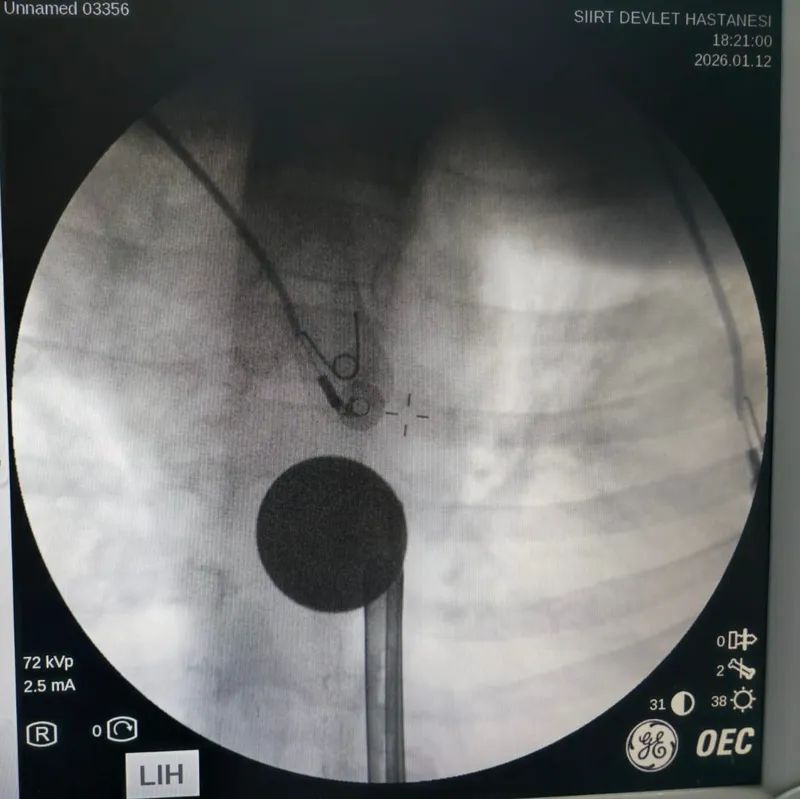

Siirt’te boğazına madeni 5 lira kaçan 8 yaşındaki çocuk, hastanede doktor müdahalesiyle kurtarıldı.

Yabancı cisim yutma şikayetiyle ailesi tarafından Siirt Eğitim ve Araştırma Hastanesine getirilen 8 yaşındaki Y.K., yapılan ilk değerlendirme ve görüntüleme tetkiklerinin ardından ilgili branşlarca operasyona alındı. Y.K.’nın yemek borusuna kadar ilerlediği tespit edilen madeni para, gastroenteroloji uzmanı Dr. Yaren Dirik ve kulak burun boğaz hekimi Yasin Gökçınar tarafından müdahale edilerek çıkartıldı. Operasyonun ardından bir süre gözlem altında tutulan Y.K., tedavisinin tamamlanmasıyla taburcu edildi.

Siirt Eğitim ve Araştırma Hastanesi Başhekim Yardımcısı Uzman Dr. Burak Özkan, çocuk hastalarda yabancı cisim yutma vakalarının ciddi riskler oluşturabileceğini söyledi. Uzm. Dr. Özkan, "Hastanemize başvuran 8 yaşındaki hastamızın yemek borusuna kaçan madeni para, gastroenteroloji ve KBB ekiplerimizin koordineli ve titiz çalışmasıyla herhangi bir komplikasyona yol açmadan başarılı bir şekilde çıkarılmıştır. Operasyon süreci sorunsuz geçmiş olup hastamızın genel durumu iyidir" dedi.